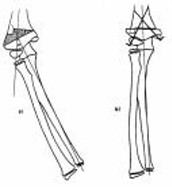

Cubitusvarus

Cong synostosis both FA-prox.

Cong synostosis both FA prox clin